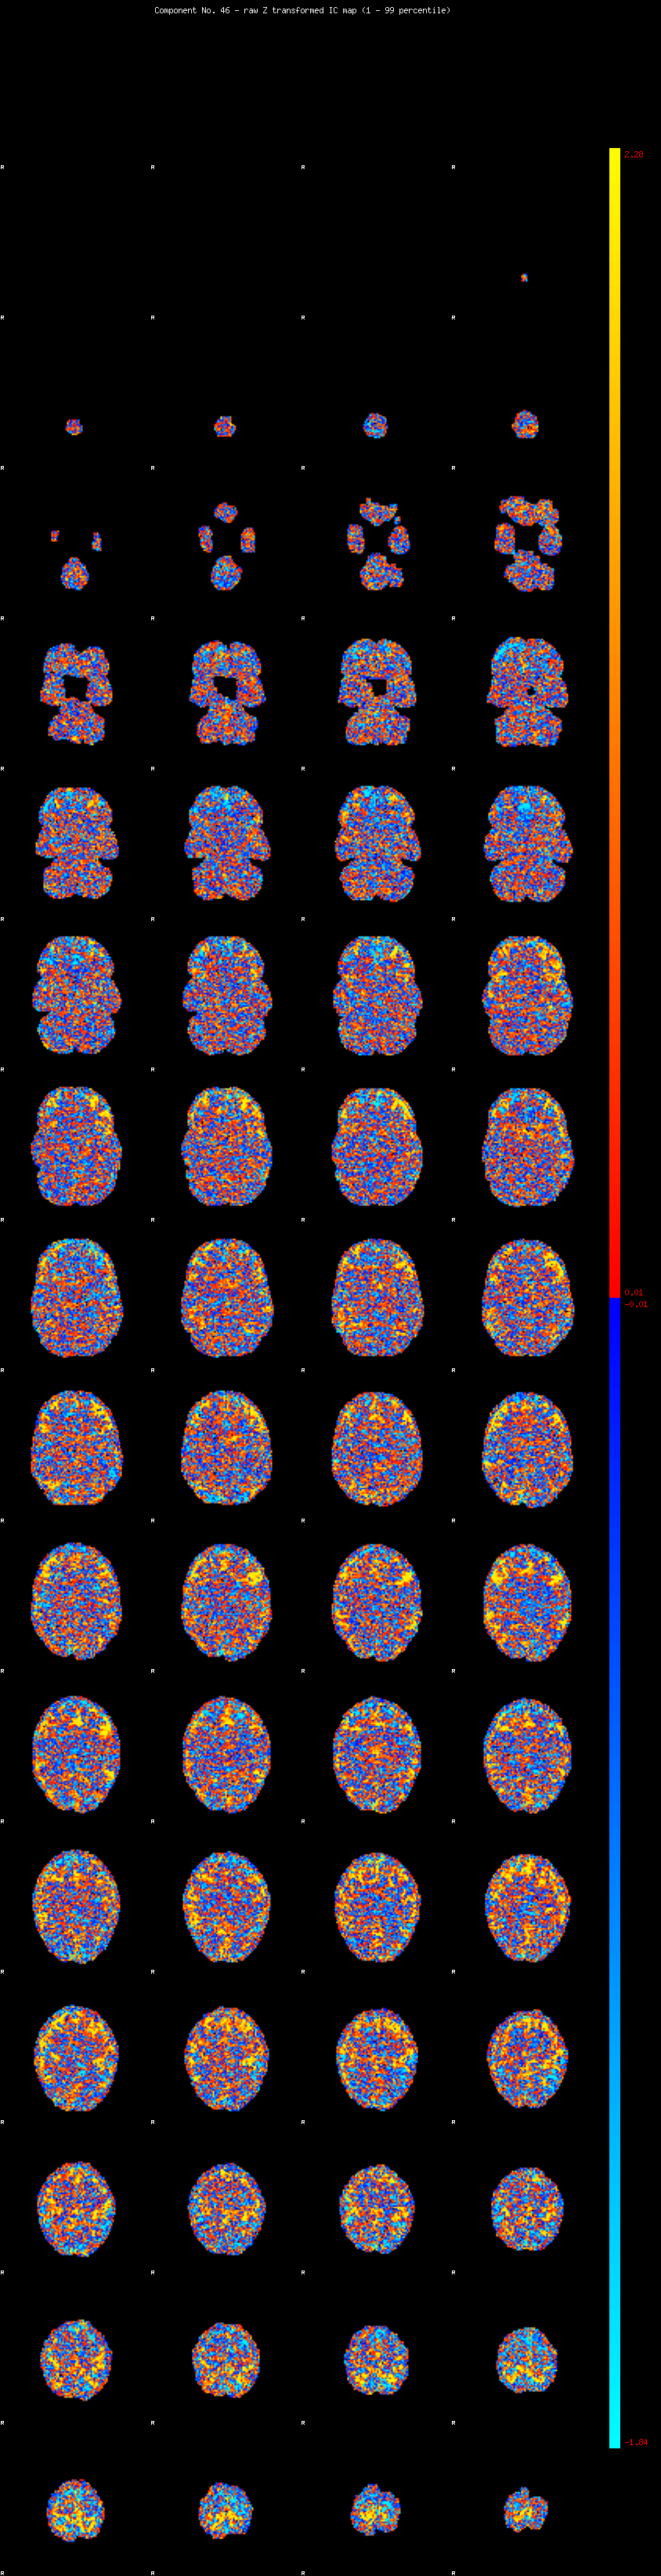

IC_46 Mixture Model fit

Means : -0.000000 2.782412 -2.630413

Vars : 1.000000 2.972189 1.102738

Prop. : 0.930828 0.054406 0.014765

This page produced automatically by MELODIC Version 3.14 - a part of FSL - FMRIB Software Library.